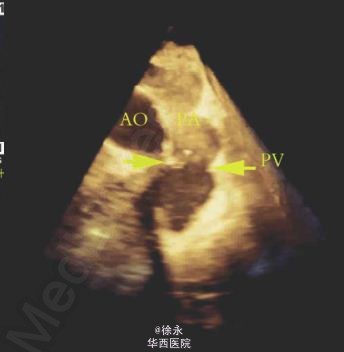

患者,女性,39 岁,25 年前因“法洛四联症”行外科治疗,近月出现活动后胸闷、心慌。超声心动图示外科术后补片下缘室水平残余分流,肺动脉瓣返流(重度)。住院期间先后行室缺残余漏封堵术+经皮导管肺动脉瓣置入术。